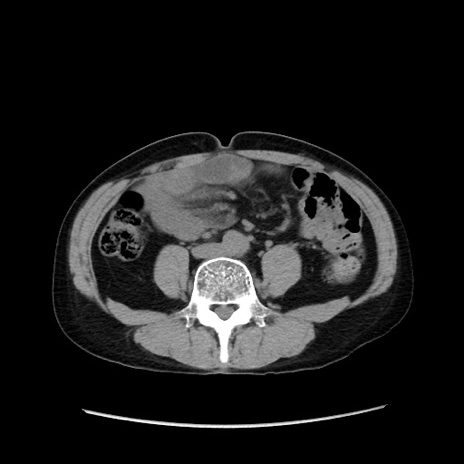

冠状断像

【症例】40歳代 男性

【主訴】腹痛

【現病歴】4時間ほど前に電車に乗車中に臍部上より腹痛出現。徐々に増悪し起立困難となり、救急外来受診。生ものは数日食べていない。今朝お雑煮を食べた。

【身体所見】BT 36.8℃、BP 117/84mmHg、HR 91/min、SpO2 97%、苦悶様、腹部:臍上部広範囲圧痛あり、反跳痛±

【データ】WBC 8100、CRP 0.03